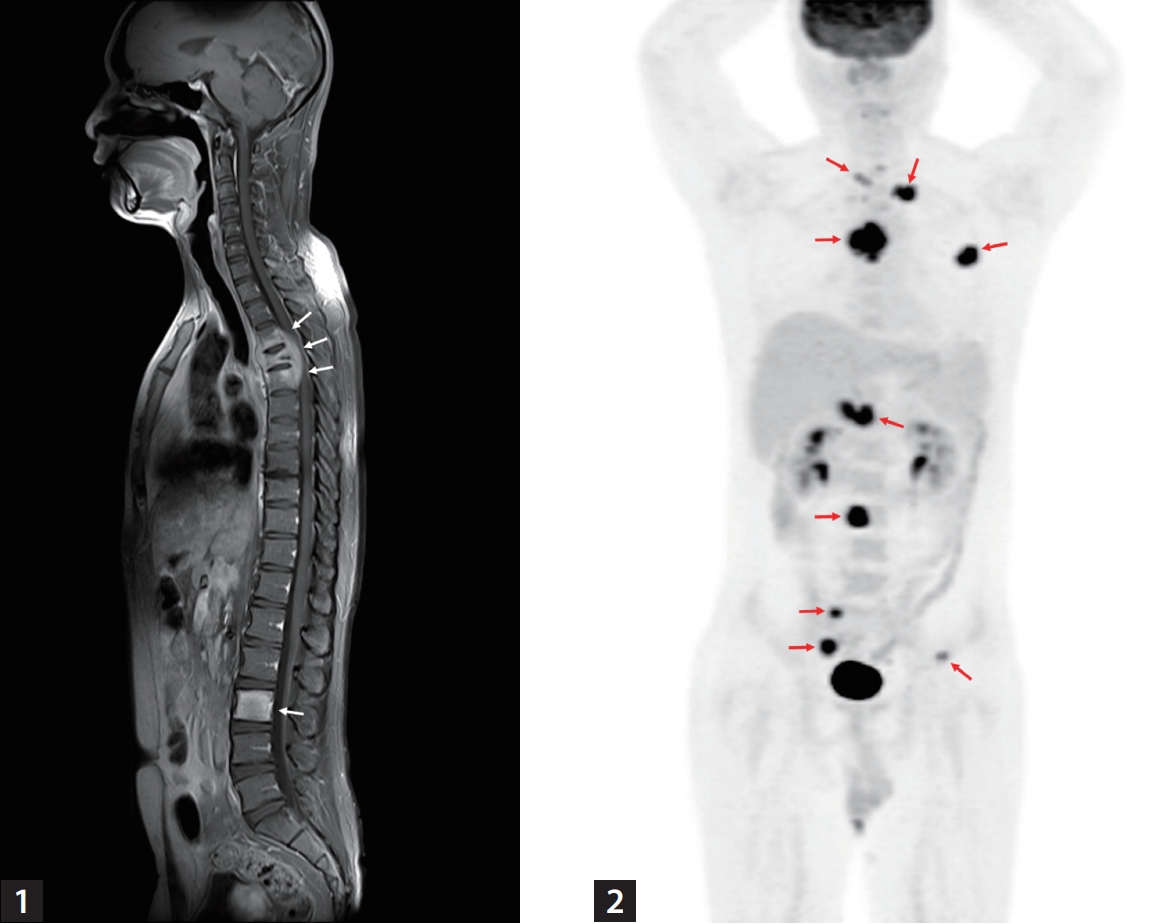

A 32-year-old man without underlying diseases presented to the emergency department with an abrupt onset of gait disturbances and a 4-week history of back pain. The patient was afebrile, and all laboratory findings were normal. Rapid plasma reagin test for syphilis was negative. Whole-spine magnetic resonance imaging revealed an abnormal signal intensity with contrast enhancement at levels T3-T5 and level L3 (Fig. 1), as well as in the right sacral alar portion and left second rib (not shown). However, chest computed tomography (CT) showed no abnormalities in the lung parenchyma, airways, pleura, or lymph nodes. Bone scan suggested bone metastases in the skull, left clavicle, left third rib, and T3-T5 and L3 vertebrae. 18F-fluorodeoxyglucose (18F-FDG) positron emission tomography/CT showed intense FDG uptake in multiple bone lesions and portocaval areas, possibly bone metastases and metastatic lymphadenopathy (Fig. 2). Percutaneous transpedicular bone biopsies were performed in the T4 and L3 vertebral bodies. Histopathological findings revealed chronic granulomatous inflammation with necrosis; however, acid-fast bacilli staining and duplex real-time polymerase chain reaction for Mycobacterium tuberculosis complex and non-tuberculous mycobacteria from fresh bone tissue were negative. On the fifteenth day after the biopsy, the mycobacterial culture from the bone specimens tested positive for M. tuberculosis complex.

Sagittal contrast-enhanced fat-suppressed T1-weighted whole-spine magnetic resonance imaging shows abnormal signal intensity with contrast enhancement at levels T3–T5 and L3 with pathologic vertebral body fracture at T4 (white arrows).